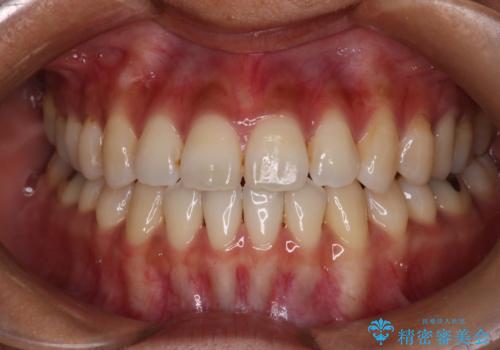

【審美装置】前歯で噛めない!抜歯しないで治したい

MARPEで非抜歯矯正|オープンバイトと八重歯を改善